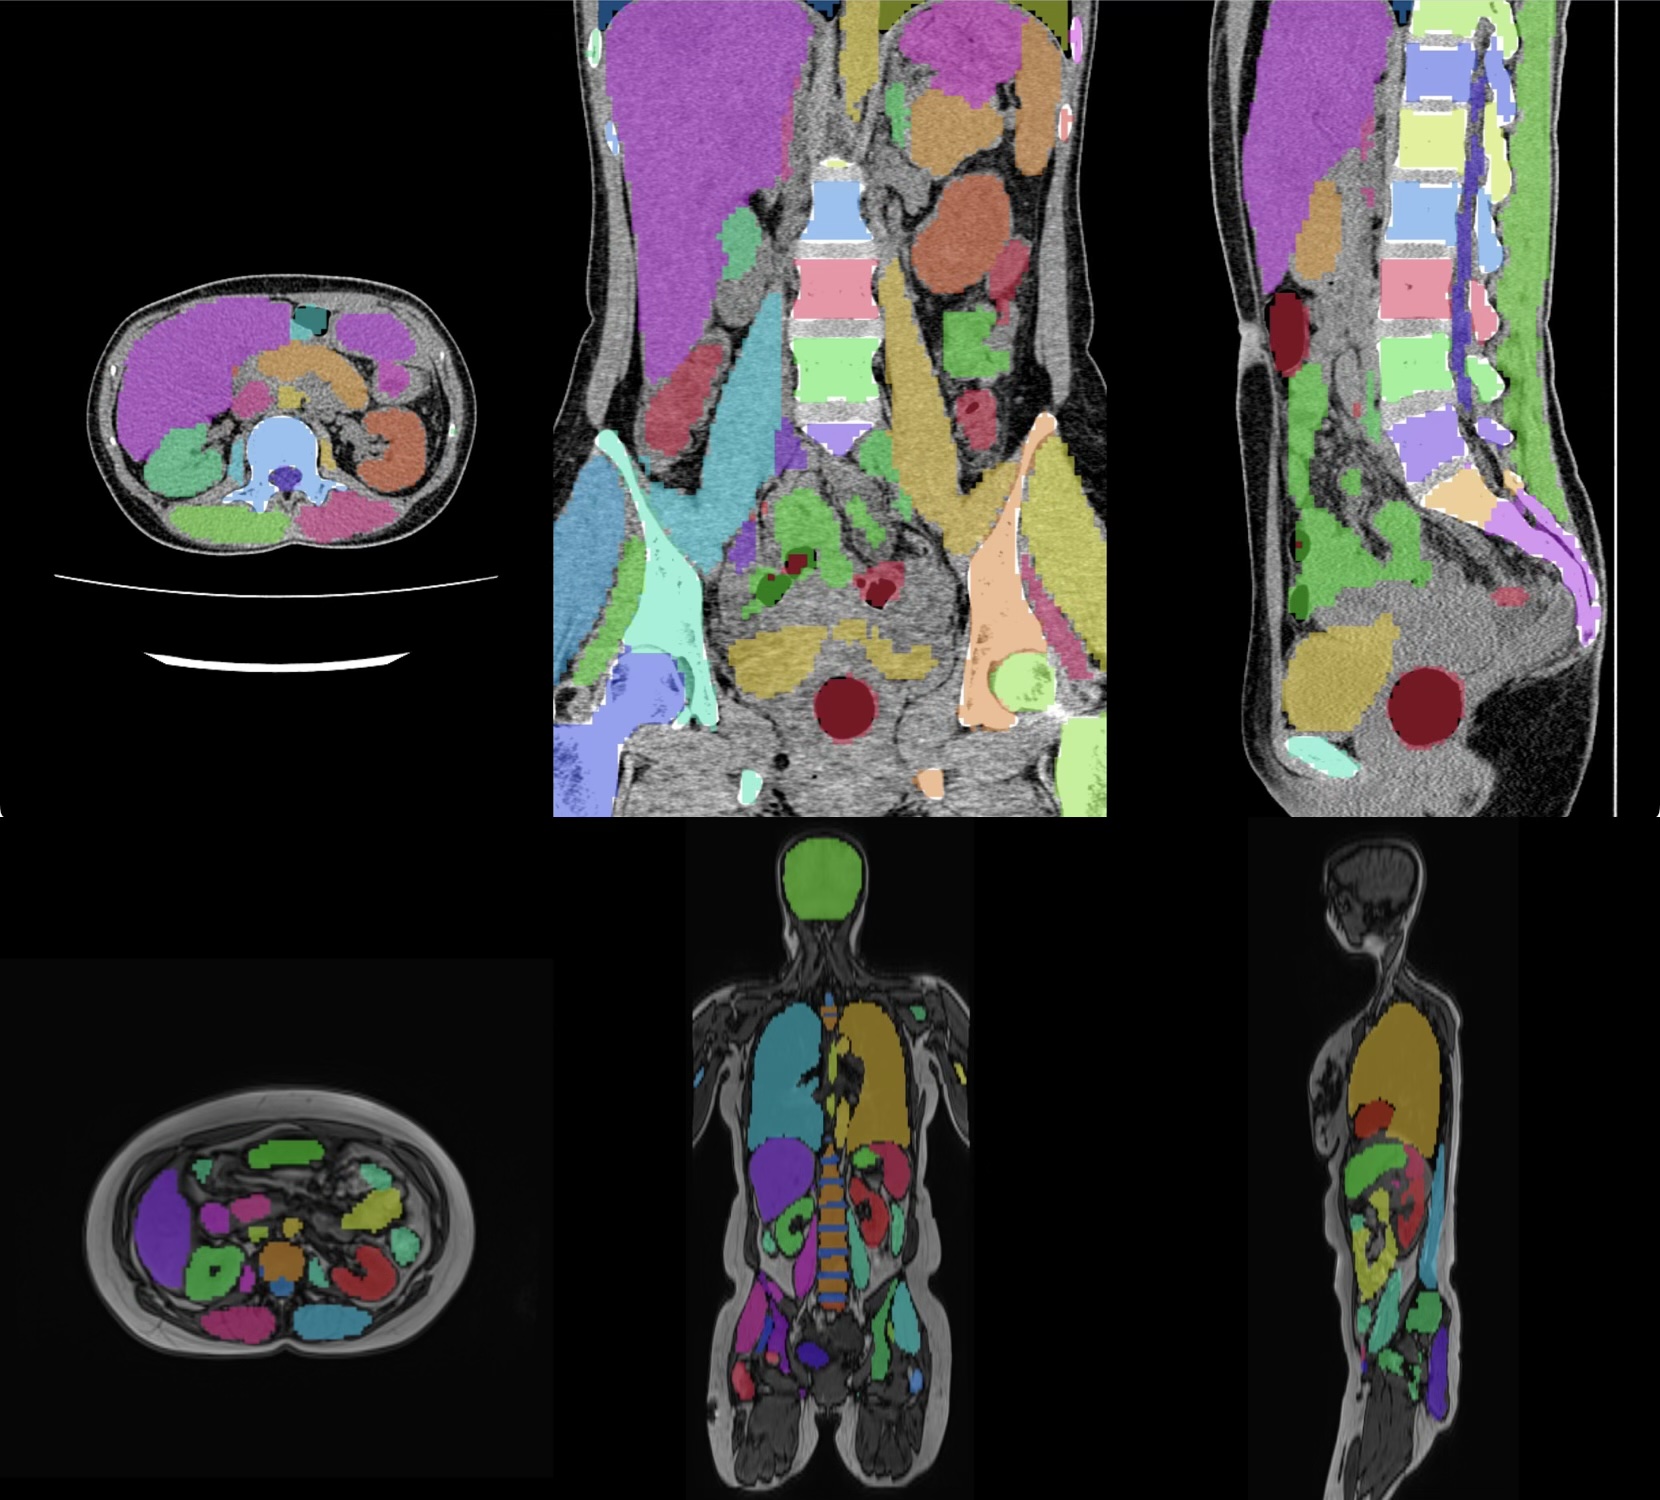

近年の生成AIの発展は目覚ましくプログラム開発の可能性を根底から底上げしている。そこでPixSpaceは純生成AIによる開発環境を構築し、0から新しいプログラム開発(試作)を始めている。完全に生成AIプログラム任せの開発であることから「Pure AI Drivenプロジェクト」と命名し、すでに3つのアプリケーションを試作した。試作の目的は開発環境・ツールとしての生成AIの可能性と限界を探るものである。試作物はそれぞれ「Protoron(プロトロン)」「Total Board(トータルボード)」「Peregrine(ペレグリン)」と名付けているが、どれも世界最先端の公開された技術を内包しているプログラム・サービスである。PixSpaceが探る技術開発の可能性を紹介したい。